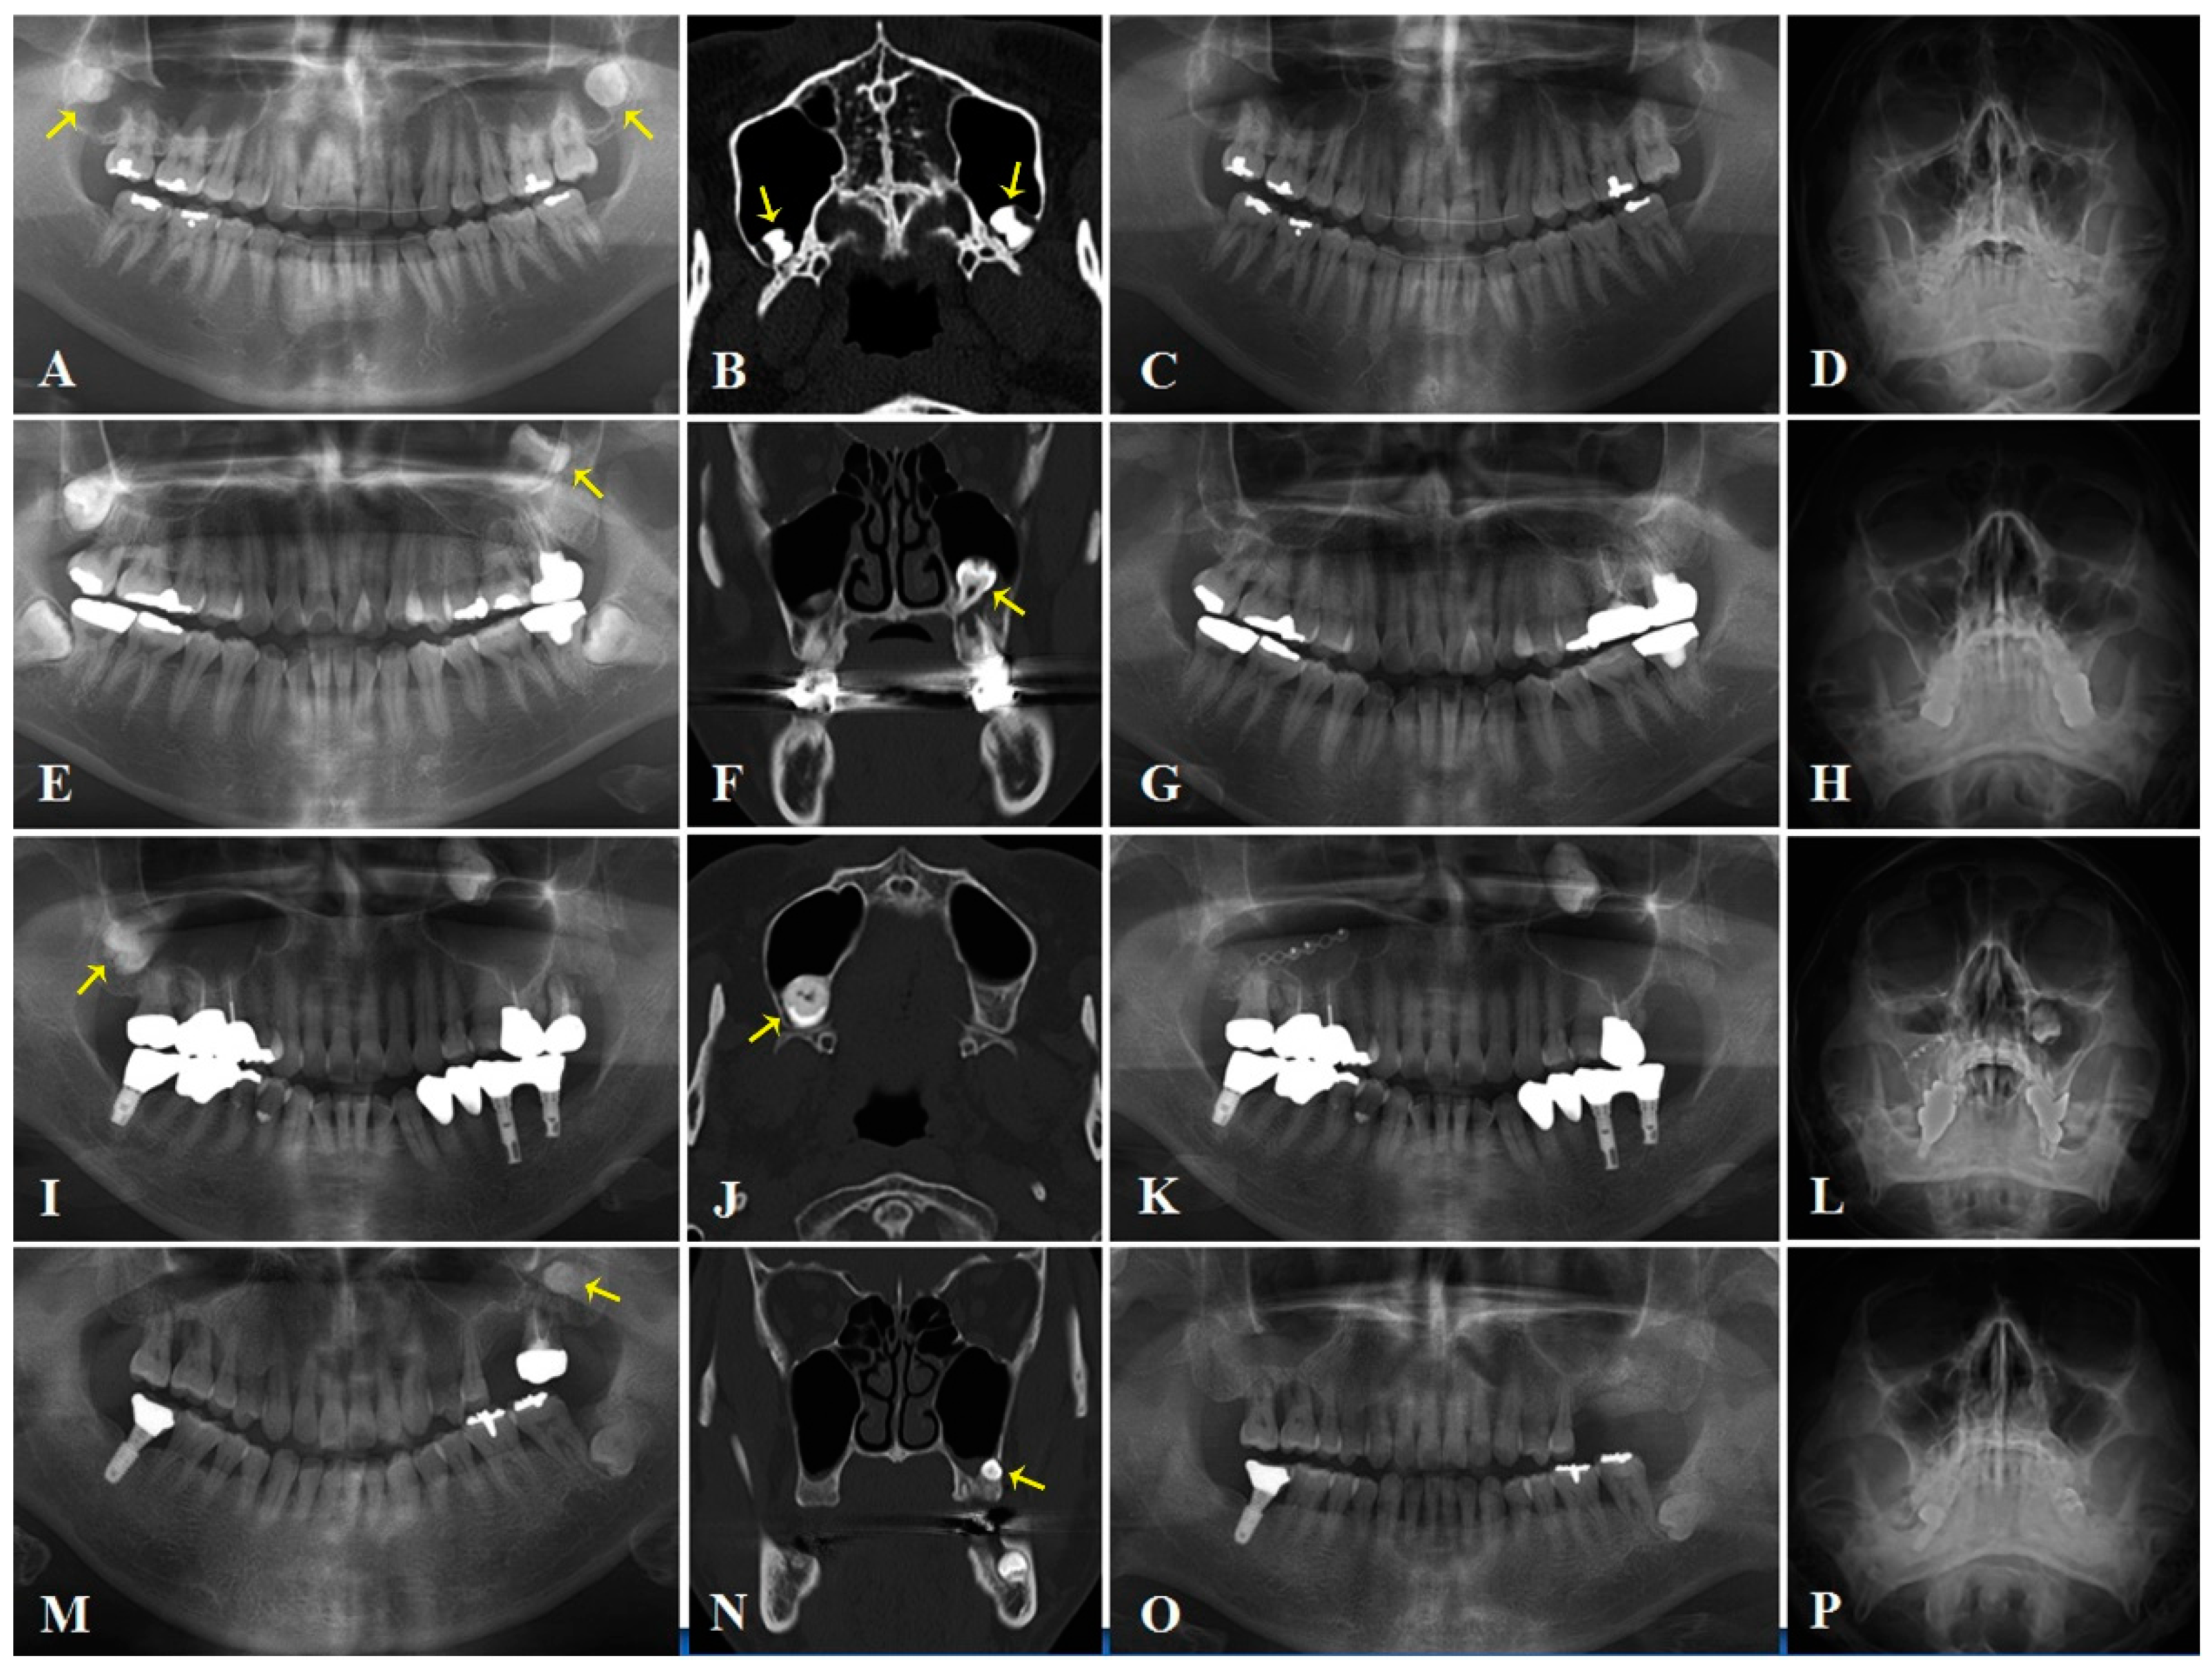

2. Case Series

2.1. Case 1

2.2. Case 2

2.3. Case 3

2.4. Case 4